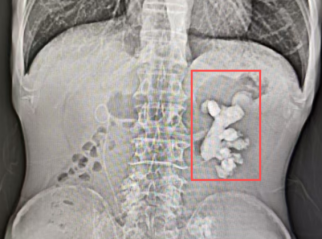

59岁的潘大叔(化名)患有肾结石已有20余年。此前,他曾在其他医院接受了右肾结石手术,而左肾结石更为复杂——最大直径达8厘米,呈铸型分布,形状如同“生姜”,几乎填满整个肾盂肾盏。

图:患者术前影像学检查

经检查,潘大叔的结石不仅体积大、分支多,硬度也极高,CT值最高达1829HU,属于临床上罕见的“极硬”结石,其硬度可与宝石级黄玉相媲美。加之结肠位置贴近肾脏,穿刺路径存在损伤风险,手术难度非常大。